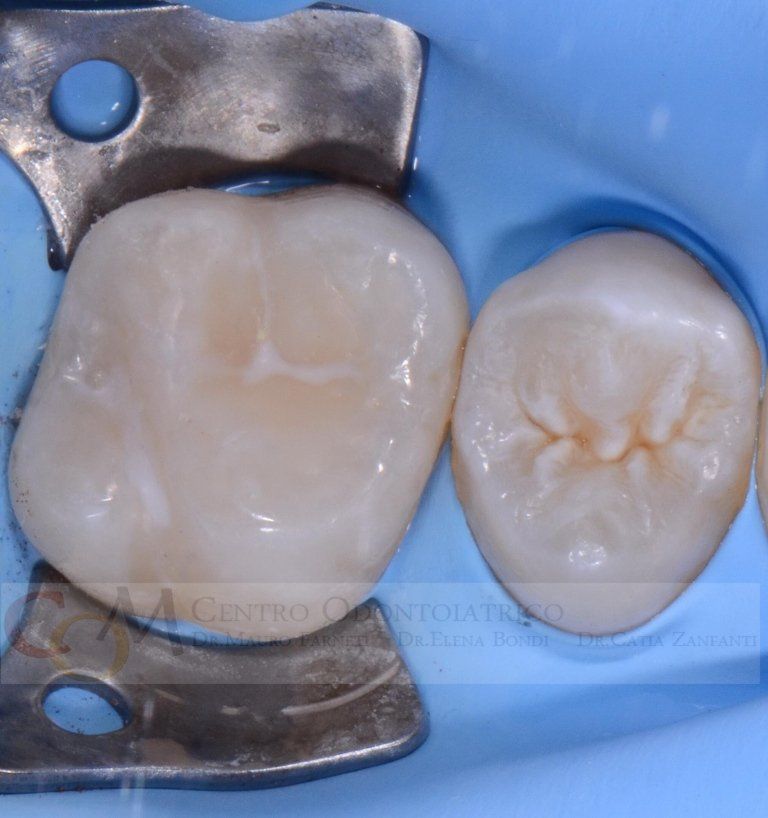

Sealing teeth is the practice of placing a "varnish", usually white in colour, on the grooves of permanent molars to

protect them from decay. If applied correctly, this procedure is extremely effective and long-lasting.

However, this practice is often carried out inconsiderately. Not all teeth need to be sealed: the morphology (i.e., shape) of the teeth, the caries susceptibility of the child, and oral hygiene at home need to be evaluated. If, based on these considerations, sealing is deemed necessary, it should be conducted according to a precise clinical protocol, which includes the application of a rubber dam (see topic in "Services"), cleaning of any pigmented grooves, and bonding of the sealant. "Forgetting" one of these steps results in poor-quality therapy: for example, sealing grooves without prior cleaning risks sealing decay underneath. Upon inspection by the dentist, these grooves would appear sealed... but so would the underlying decay, which wasn't removed, making it invisible. This would result in dental decay that cannot be diagnosed in its early stages as it is "covered" by the dental sealant... truly not a good job! Below are examples of correctly sealed and emblematic cases of how sealing should NOT be performed.